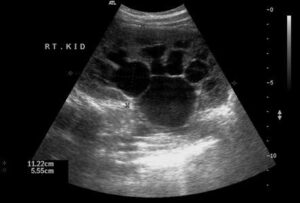

Böbrek Taşı